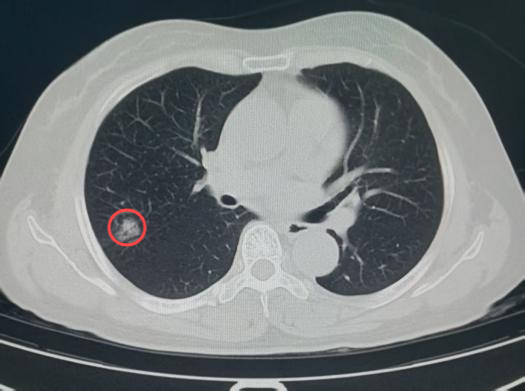

放射影像科在诊断过程中,借助AI肺结节筛查软件,敏锐捕捉到王女士右侧肺叶存在一个大小约17×22mm的部分实性结节。不仅如此,系统还迅速调取了她2023年在该院体检时的影像资料。影像科医生仔细比对后发现,虽然2023年王女士右肺叶的结节已存在且大小无明显变化,但结节的质地从磨玻璃样转变为少许实性的混合磨玻璃样,边界进一步清晰,边缘还出现了浅分叶及短毛刺等典型的恶性征象。与此同时,AI筛查软件也发出警示,将该结节的危险程度判定为“高危”。即便王女士自述并无任何呼吸系统症状,凭借专业的判断,影像科还是高度怀疑该结节存在肿瘤性病变的可能。

(2023年结节影)